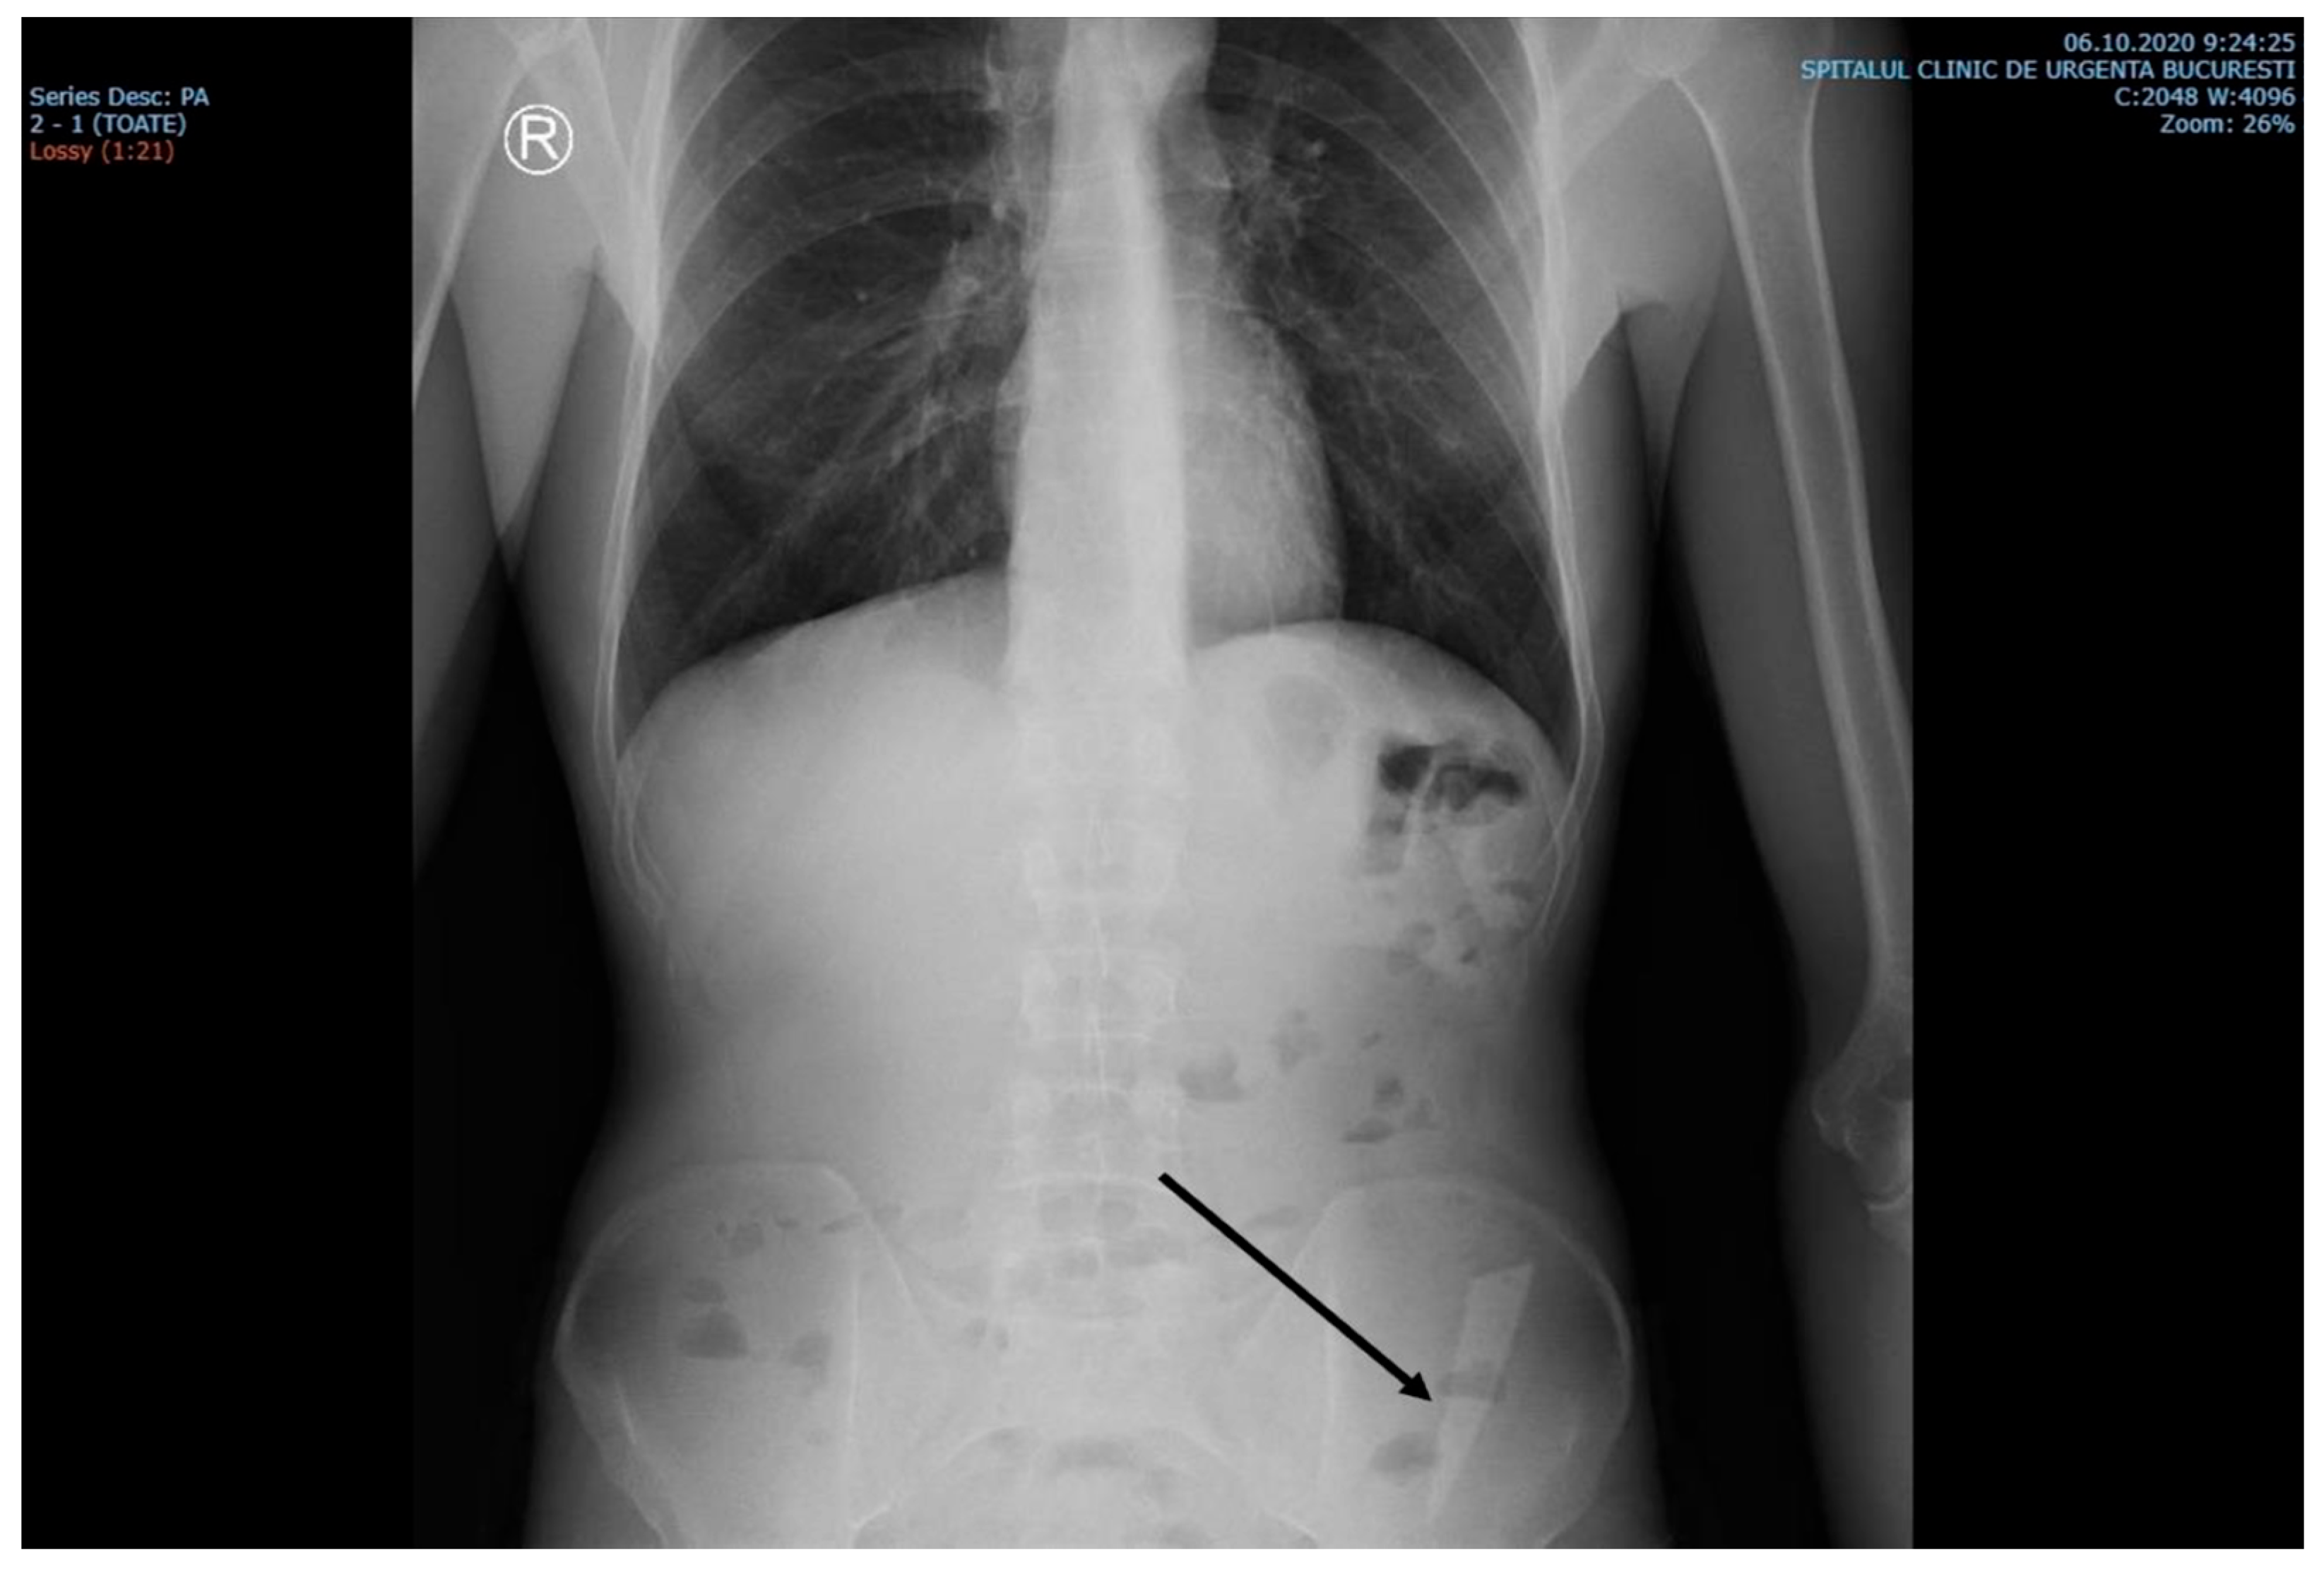

A CT scan performed before admittance showed, in the left iliac fossa, a foreign body with a density similar to the bone cortex, without reaching the specific density of the metal, and with an elongated shape similar to a knife blade tip (dimensions: 7.5 cm long at the base, 2 cm wide, and 4 mm thick). Most of this foreign body was located in the descending colon at the junction with the sigmoid. The tip of the foreign body was oriented craniocaudally and ventrally. It crossed the digestive wall and reached a transperitoneal position in the right abdominal muscle, on the left side, passing tangentially to the left lower epigastric vessels. In this region, the colonic wall appeared moderately thickened. There were small local intraperitoneal pericolic gas bubbles, no local fluid collections, no ascites, no pneumoperitoneum, and no signs of occlusion (Figure 2).

Figure 2. Contrast-enhanced abdominal CT revealed the presence of a foreign object in the left iliac fossa.